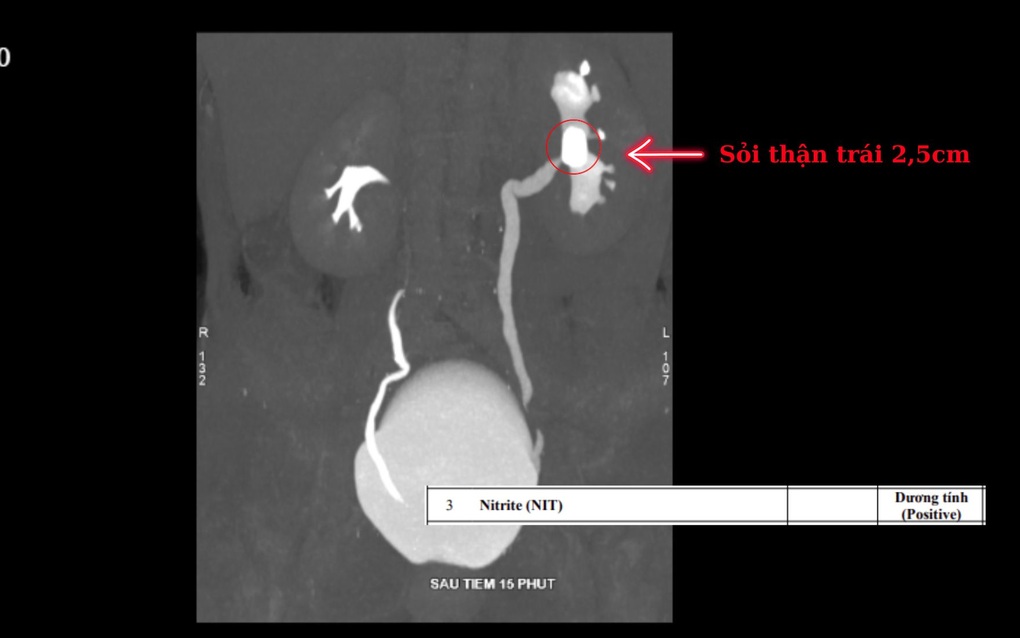

Bà H. vào BVĐK Hồng Ngọc trong tình trạng sốt cao, rét run, đau dữ dội vùng hông lưng phải. Sau khi tiếp cận quy trình cấp cứu chuyên khoa và được thực hiện các xét nghiệm, chẩn đoán hình ảnh cần thiết (siêu âm, CT-Scan), bệnh nhân được xác định có một viên sỏi kích thước lớn đến 2,5cm nằm trong đài bể thận bên trái. Đây là nguyên nhân gốc rễ gây ra tình trạng đau lưng kéo dài cho bệnh nhân, từ đó biến chứng nhiễm trùng đường tiết niệu và ứ mủ thận trái, khiến bệnh nhân phải nhập viện cấp cứu.

Sỏi thận kích thước lớn kèm nhiễm khuẩn đường tiết niệu (Ảnh: BVCC).